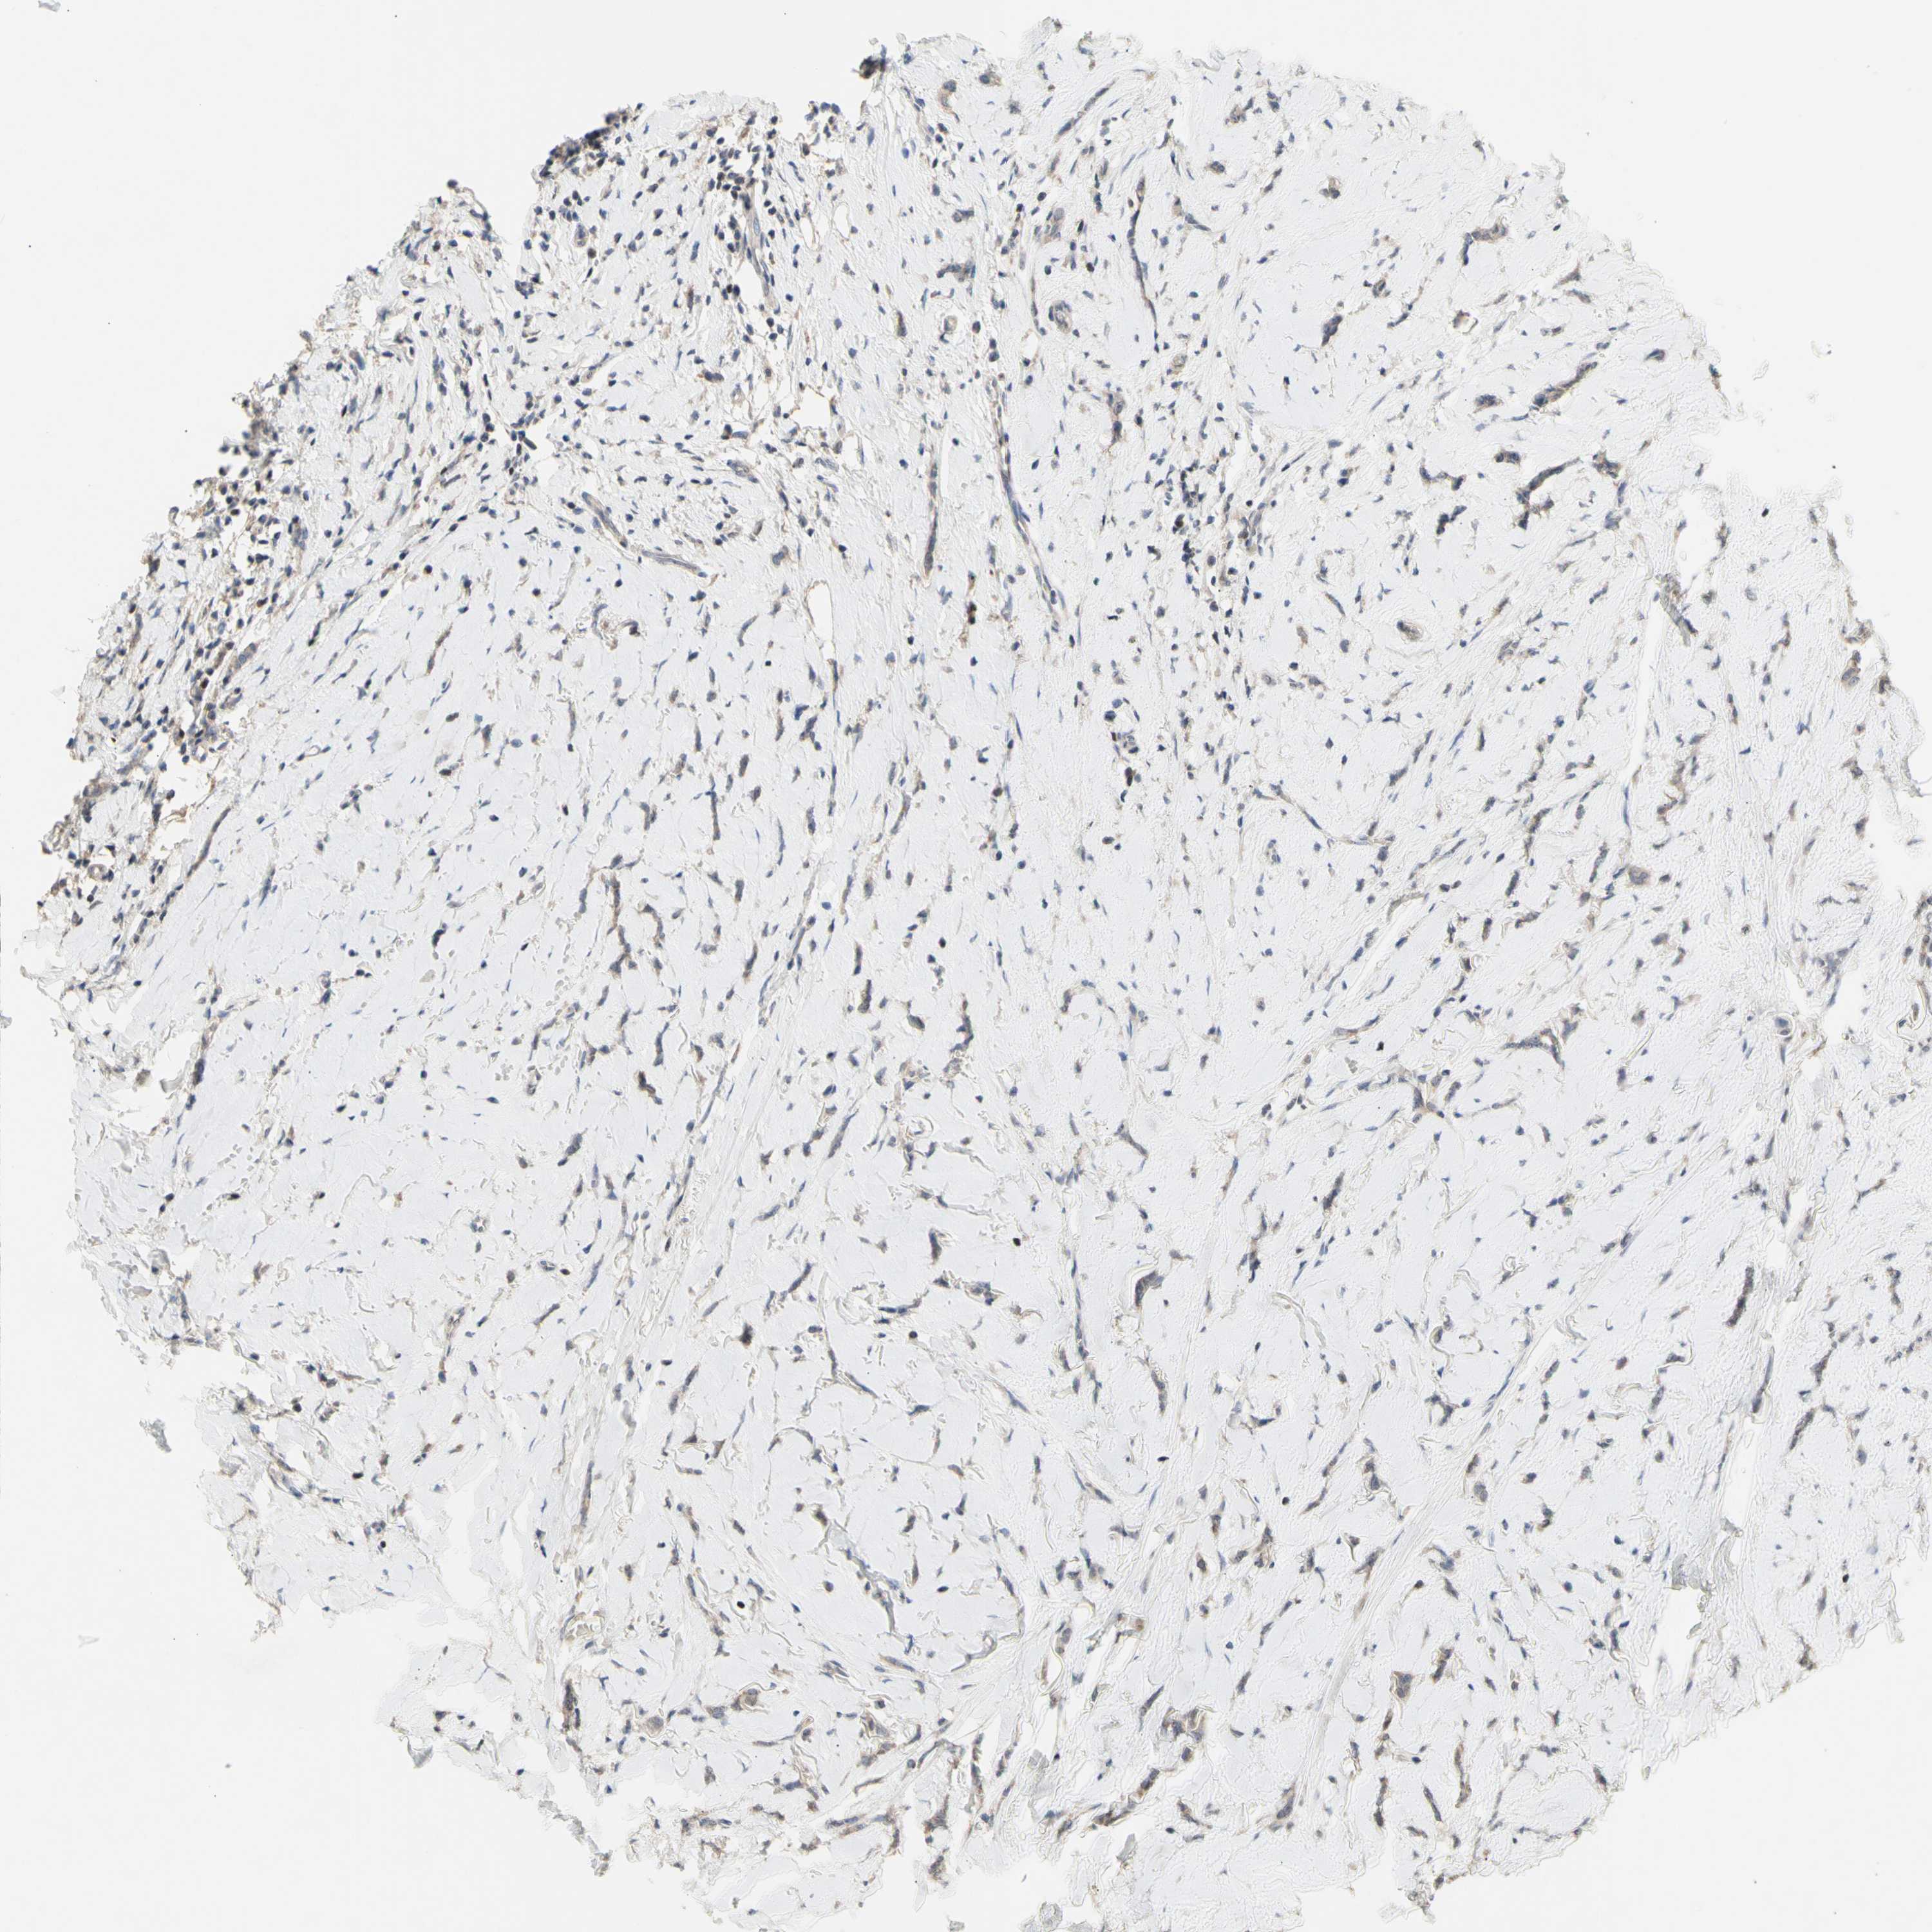

CANCER BREAST CANCER Show tissue menu

BRCA TCGA BRCA VALIDATION PROTEIN EXPRESSION